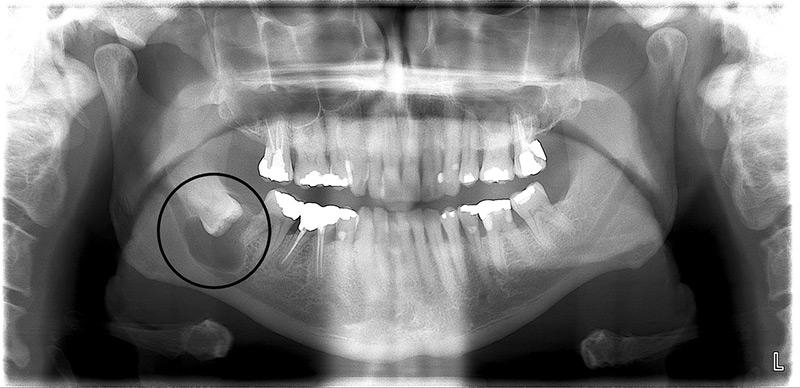

A small dental cyst developing inside the jawbone may be visible on an X-ray. Larger cysts may cause a firm facial swelling to appear. Your teeth may also start migrating rapidly in the area affected by the cyst.

Periodic dental x-rays are essential for identification of dental cysts and other bony abnormalities.

Dental cysts are normally picked up during a routine examination,which includes dental x-rays.

Your dentist may order a 3D CBCT scan that will provide more information about the cyst and its relationship with surrounding teeth and other structures (nerves, sinuses) within the bone.